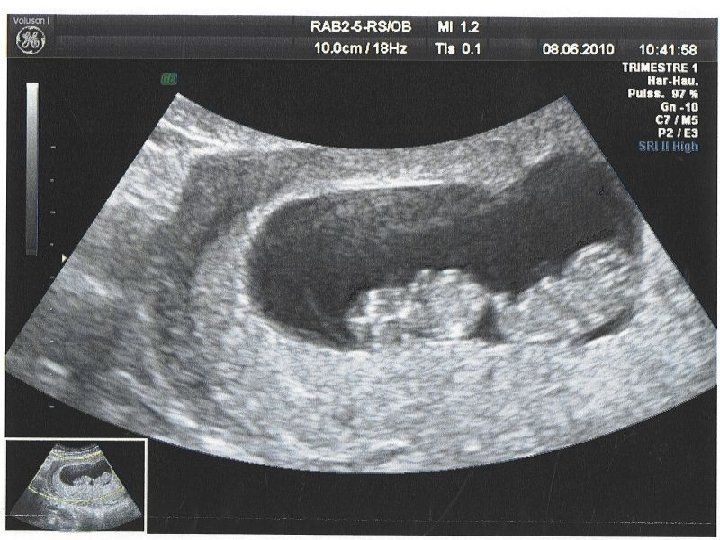

C- EXAMENS PARACLINIQUES : 1 - ECHOGRAPHIE : Le diagnostic est possible dès 8 SA de grossesse gémellaire mono chorialebi amniotique (membrane fine de séparation), ou bi chorialebi amniotique (membrane de séparation épaisse). 2 - RADIOGRAPHIE DU CONTENU UTERIN : Confirme le diagnostic en fin de grossesse, Précise la position des fœtus. 3 - ERCF : Mise en évidence de deux rythmes cardiaques différents.